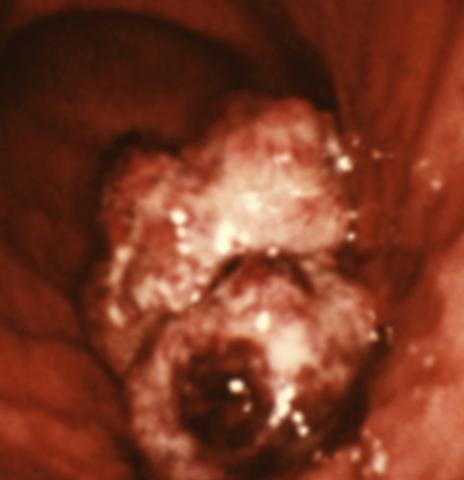

Рис. 14. Эндоскопическая картина желудка в норме и при различных заболеваниях. Рак желудка (экзофитная форма роста): в средней трети желудка по большой кривизне определяется полиповидная, неправильной формы опухоль с фибринозным налетом и очагами кровоизлияний.